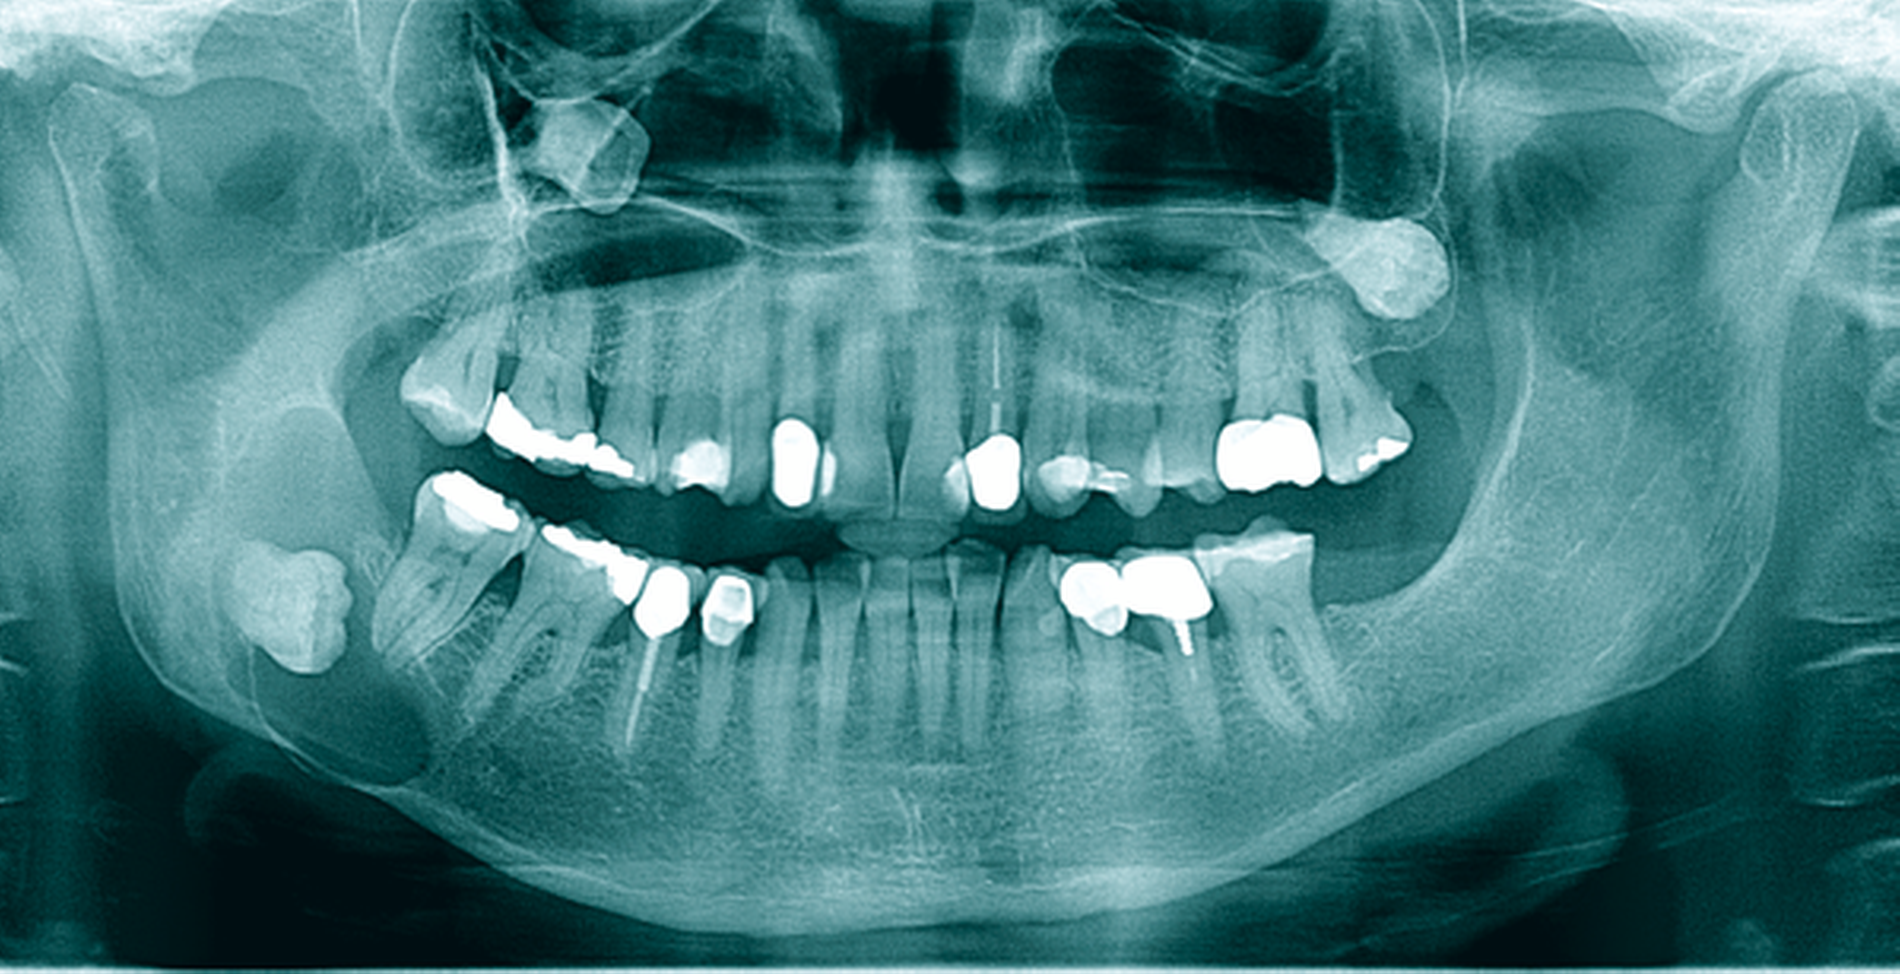

Eine 72-jährige Patientin wurde zur Therapie einer Zyste in regio 48 in unser MVZ überwiesen. Es handelte sich um einen Zufallsbefund im OPTG. Klinische Beschwerden wurden von der Patientin verneint (Abbildung 2a). Vorerkrankungen bestanden abgesehen von Migräne nicht. Zur Beurteilung der Zystenausdehnung erfolgte eine Computertomografie des Gesichtsschädels, die insbesondere eine basal stark ausgedünnte Kortikalis zeigte. Nach Erörterung der therapeutischen Möglichkeiten entschied sich die Patientin für eine Zystostomie, da die Zystektomie mit einem erheblichen Frakturrisiko, der möglichen Schädigung des N. alveolaris inferior sowie einer Behandlung in Allgemeinanästhesie verbunden gewesen wäre. In Lokalanästhesie wurde über einen marginalen Zugang in regio 47-48 eine Biopsie des Zystenbalgs gewonnen sowie eine Drainage ins Zystenlumen inseriert. Histologisch konnte eine follikuläre Zyste gesichert werden.

Die täglichen Spülungen des Lumens über die einliegende Drainage mit NaCl-Lösung erfolgten durch die Patientin selbst nach entsprechender Instruktion. Dies führte sie für sechs Monate selbstständig durch. Zwischenzeitlich musste das Drainageröhrchen wegen Verlusts erneut inseriert werden. Im DVT zeigte sich nach sechs Monaten eine signifikante Ossifikation am Rande des Zystenlumens und der N. alveolaris inferior wies wieder eine knöcherne Ummantelung auf (Abbildung 2b). Somit konnten die Zystektomie des verbliebenen Befunds und die Entfernung von 48 in ITN erfolgen. Dabei und postoperativ traten keine Komplikationen auf. Zahn 47 ist unverändert vital. Die extrem verlagerten Zähne 18 und 28 wurden auf Wunsch der Patientin belassen. Nach vier Monaten stellt sich im OPTG ein nahezu vollständig ossifizierter Defekt dar und die Patientin ist vollkommen beschwerdefrei (Abbildung 2c).